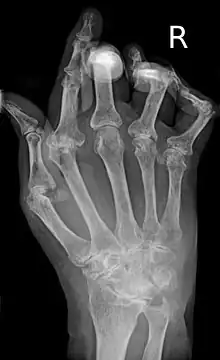

As the pathology progresses the inflammatory activity leads to tendon tethering and erosion and destruction of the joint surface, which impairs range of movement and leads to deformity. The fingers may develop almost any deformity depending on which joints are most involved. Specific deformities, which also occur in osteoarthritis, include ulnar deviation, boutonniere deformity (also "buttonhole deformity", flexion of proximal interphalangeal joint and extension of distal interphalangeal joint of the hand), swan neck deformity (hyperextension at proximal interphalangeal joint and flexion at distal interphalangeal joint) and "Z-thumb." "Z-thumb" or "Z-deformity" consists of hyperextension of the interphalangeal joint, fixed flexion and subluxation of the metacarpophalangeal joint and gives a "Z" appearance to the thumb.[16]: 1098 The hammer toe deformity may be seen. In the worst case, joints are known as arthritis mutilans due to the mutilating nature of the deformities.[20]